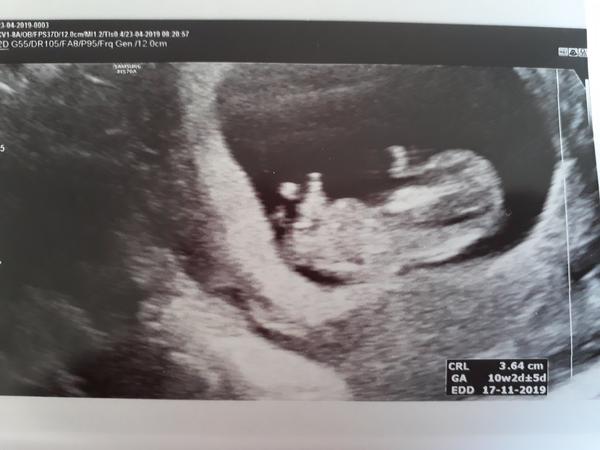

Je běžné, že na UZ v 11 týdnu nevidím končetiny? A kde najdu placentu?

1)Kde na obrázku mohu spatřit placentu ?

2)Je běžné že v 11 tydnu nevidím končetiny?

Mimco se urcite ,,pri foceni" hodne mrskalo. Ale ma je tam! 😊Placentu si myslim, ze vidim. Ale treba odpovi nekdo odbornejsi. 😉

@patmouse já vím , ve středu jako na počátku nejsem , jen prostě mě zajímá jestli placenta je např někde ve předu což by asi vysvětlovalo že ho slyším poslední týdny a ta poslední třeba tři dny vůbec ...a končetiny jsem neviděla ,, mrskat " ani na tom USG ..je mi jasný že kdyby bylo něco blbě nepisu sem ..jediný co z obrázku poznám je hlava a toť vše

@gruyerre já si taky myslím že to vybouleny , ale nebyla sem si tím jistá , třeba na tvým obrázků to vybouleny není .Ne že bych tě chtěla strašit , ale zajímá mě ciste že zvědavosti , jak vlastně ti doktoři tu placentu najdou , na googlu pokaždý vyskočí jiný obrázek a placenta je popsána pokaždý jinde a jinak .😊Tak mě zajímalo třeba , zda se to určuje podle nakyho ,, projasnění " či tak

Placenta se utváří na na konci 1. trimestru. Do té doby vyživuje dítě tzv. žloutkový váček. Vak blan, pupečník a placenta přebírají funkci až kolem 12. týdne, takže na UZ nemusí být viditelné v 11. týdnu.

Musíš si uvědomit, že utz je 2D, tedy jde o řezy, placky. Nejde o fotku, jde o průřez. Tedy v určitém okamžiku může chybět i hlava, přesto ji mimino má 😉 A stejně je to i s končetinama. Placenta vidět není, teprve se utvořila plně, teď se může různě posouvat kontrolu od kontroly, jak všechno uvnitř rychle poroste. Na její polohu se klidně zeptej, ale lékař ti to dost možná ani nesdělí, pokud není problematicky uložená. A i na takový soud je příliš brzy, i kdyby byla přes celý čípek shora, vytáhne se.

@lery92 zde je obrázek 😂😂😂, já mám takový nervy že sem ho zapomněla přiložit